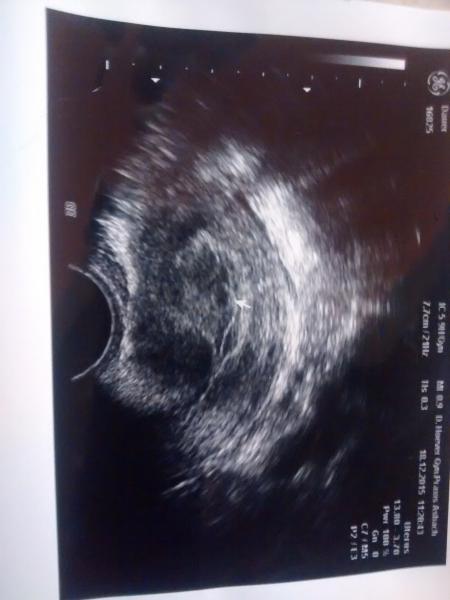

Hab mal mein erstes Ultraschall Bild mit begefügt wo ich laut FA ssw5 war...Hab vom kh leider keins mitbekommen habe aber mal gegoogelt da sehen die Bilder von ssw 6 eher so aus wie das was man im kh sehen konnte.. Ich will die Hoffnung noch nicht aufgeben

Bild zu